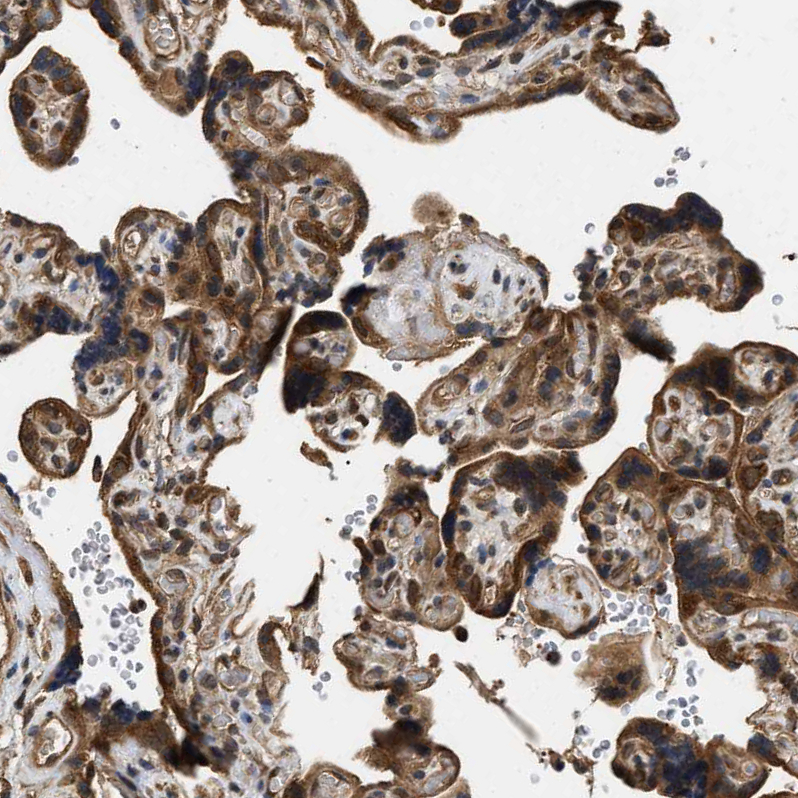

Immunohistochemical staining of human testis shows strong cytoplasmic positivity in cells in seminiferous ducts.